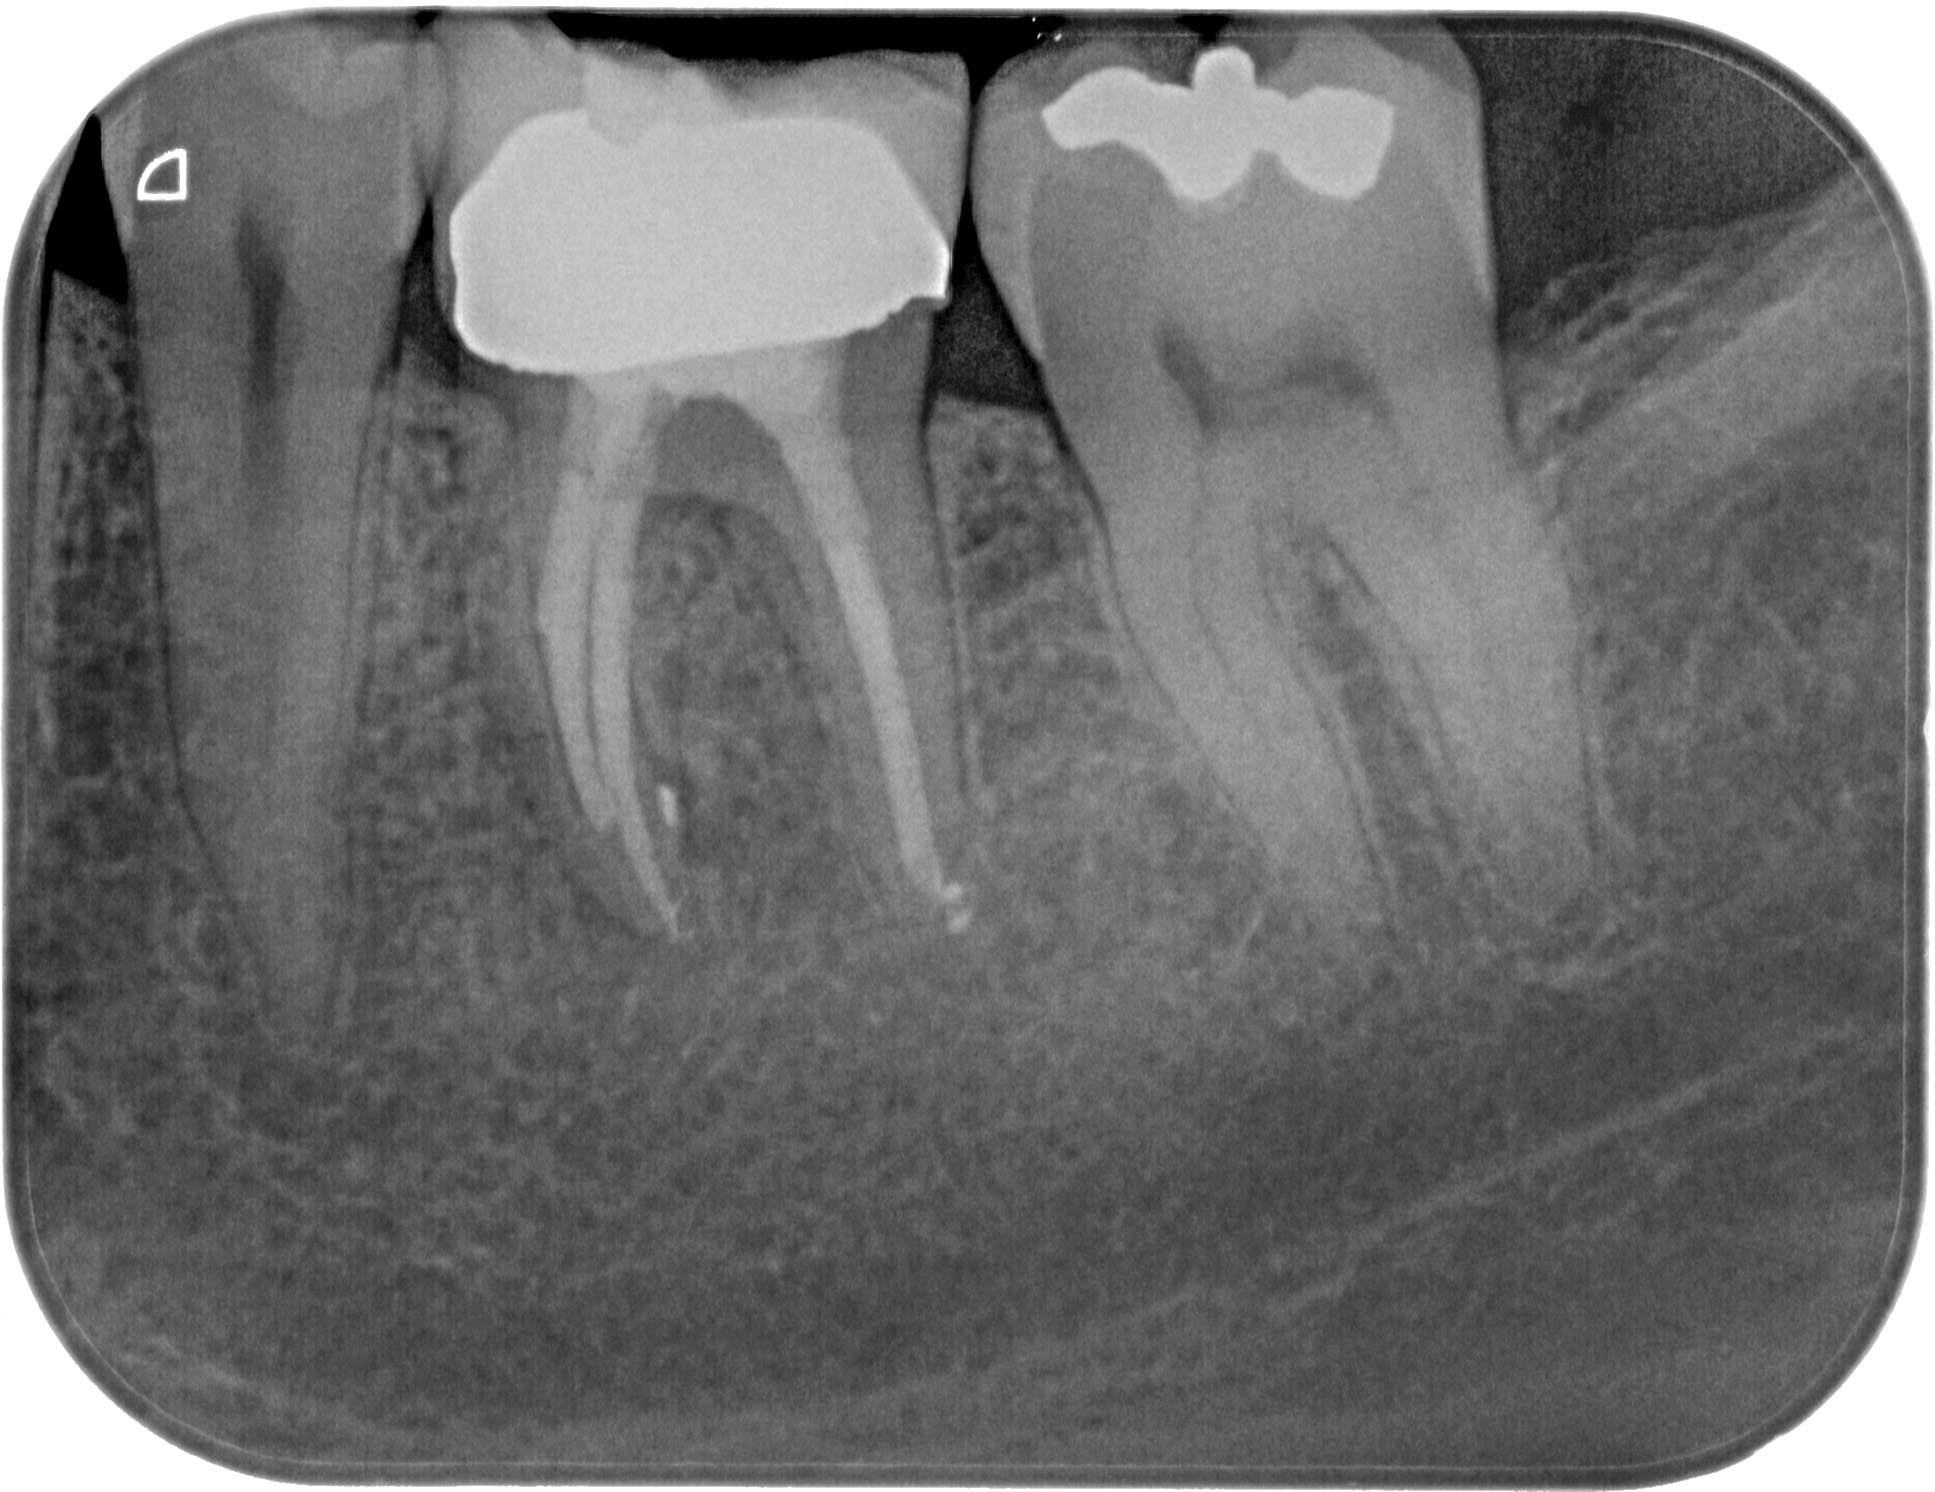

FM36 (4 von 6) Veröffentlicht 21. März 2016 am 1935 × 1492 in Calciumhydroxid- Überpressung (2) 21. Februar 2014